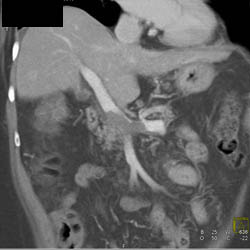

Liver Metastases